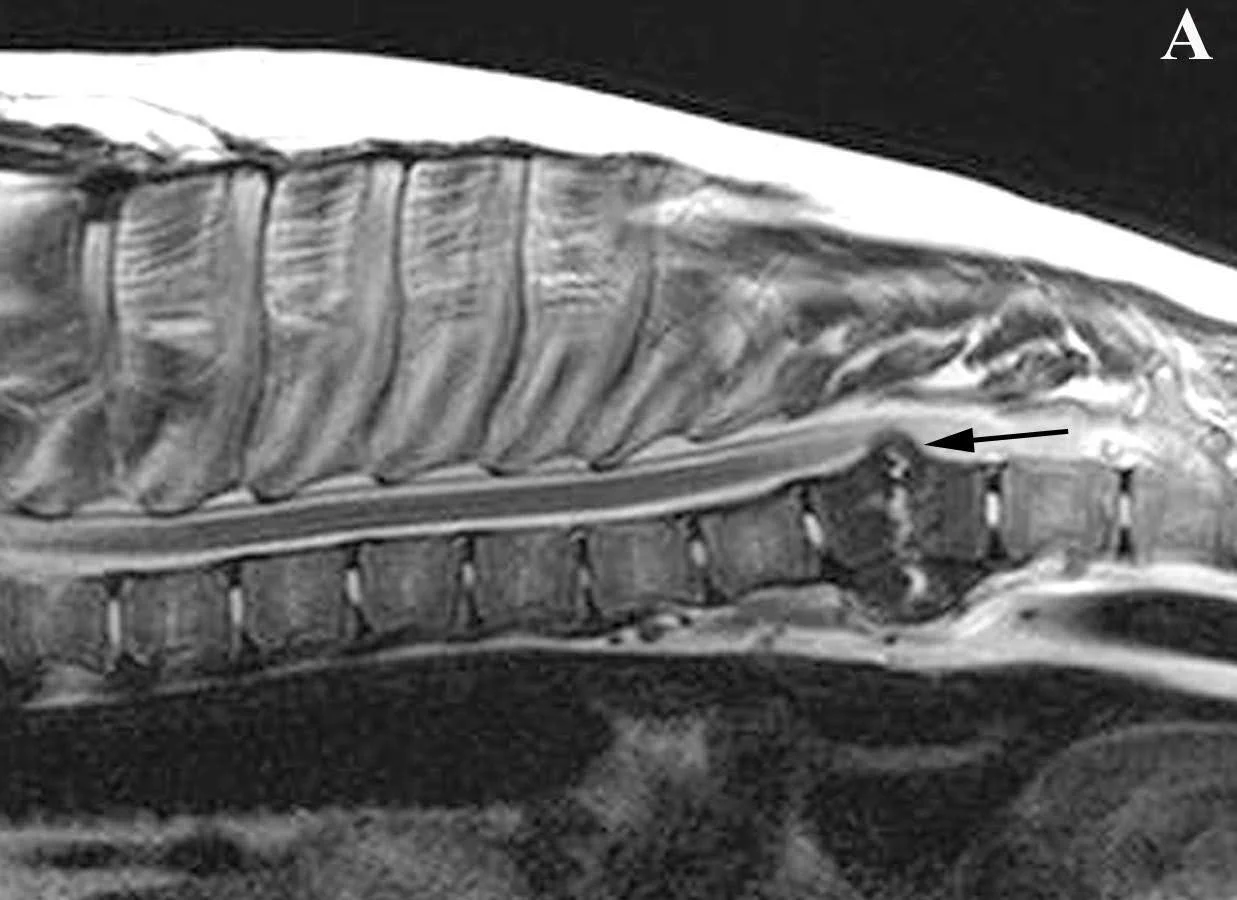

MRI scan showing Diskospondylitis in a dog with spinal cord compression.

Magnetic Resonance Imaging (MRI) of a male 10-year-old Chesapeake Bay Retriever presenting for back pain and weakness in his back legs. A sagittal T1 W post-contrast image of the thoracic vertebral column and spinal cord is shown. At T8-9, there is dramatic sclerosis of the vertebral bodies, erosions of the vertebral endplates (caudal endplate of T8 and cranial endplate of T9), and contrast-enhancing material within the disk space. The material within the disk space protrudes into the spinal canal, causing severe compression of the spinal cord.